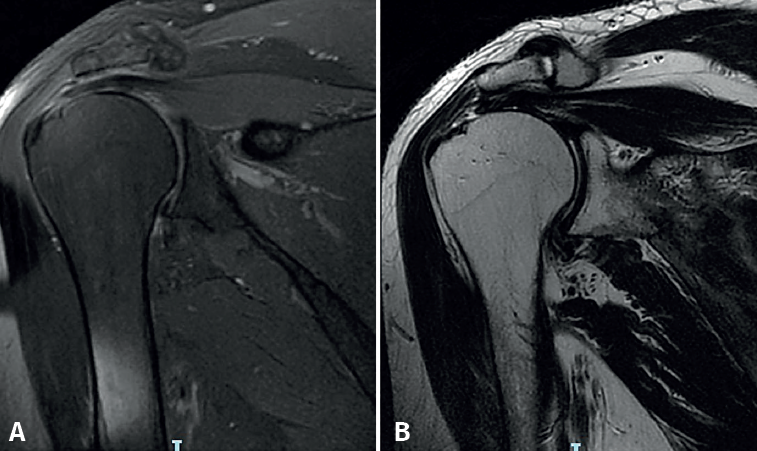

Reduction phase in the second row (Figure 2A)

In the reduction phase in the second row, the tendon is reduced to its footprint by knotting the Loop Lasso®traction stitches at its free margin with the sutures of the anchors of the second or central row. The two strands of each suture are retrieved together in the subacromial space through the PSL portal for the posterior anchor and the ASL portal for the anterior anchor. Knotting is started at the most posterior suture while maintaining traction reduction of the anterior sutures. The type of knot used is the so-called easy knot, followed by half stitches to complete a "surgeon's knot" configuration. The same procedure is carried out successively on the other three sutures, and the remaining strands are cut.